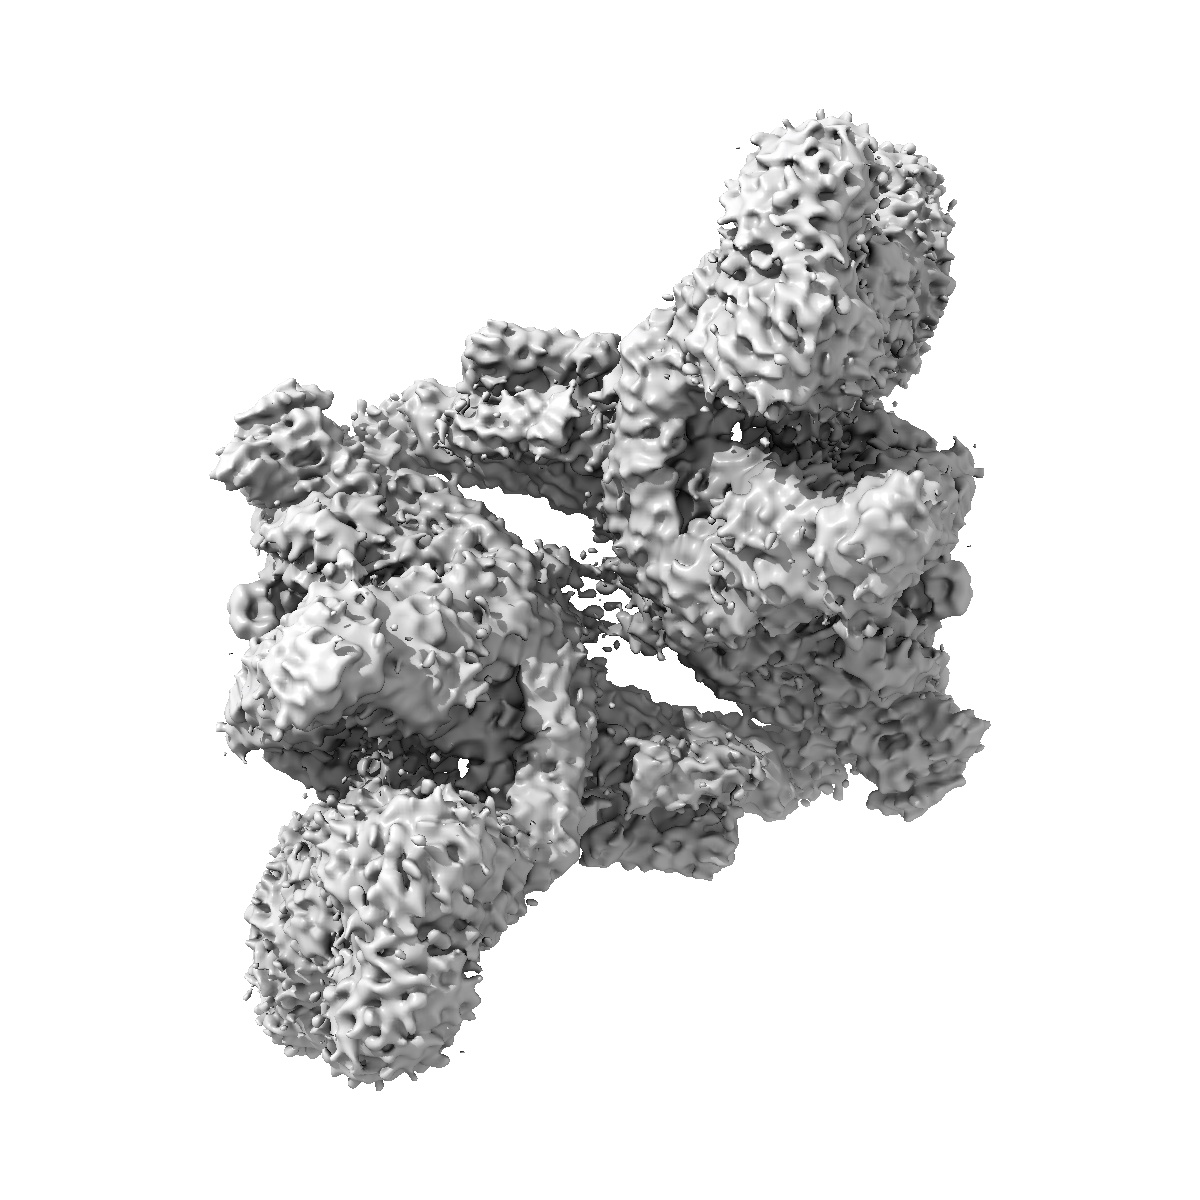

SARS-CoV-2 Replication-Transcription Complex has a dimer architecture (dRTC) in post-capping state

Sample: post capping initiation RTC

Structural basis for the concurrence of template recycling and RNA capping in SARS-CoV-2.

Yan L, Huang Y, Liu Y, Ge J, Gao S, Tan L, Liu L, Liu Z, Ye S, Wang J, Xiong J, Zhou Y, Zhao H, Zhao X, Guddat LW, Gao Y, Zhu L, Rao Z, Lou Z

(2025) Cell , 188 , 7194 - 7205.e10